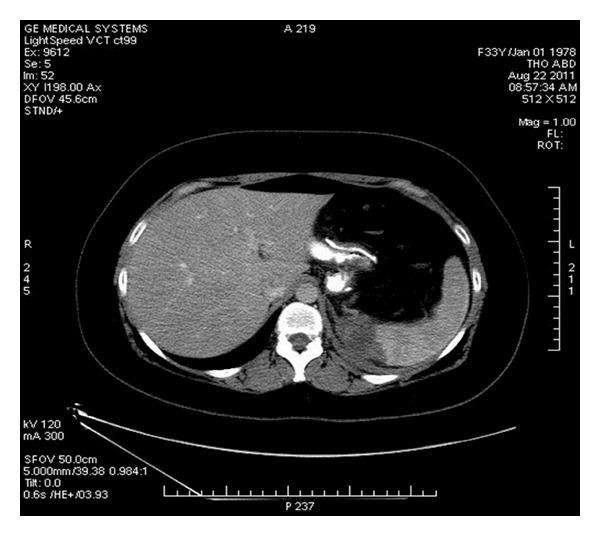

针对轻度肥胖患者(体重指数为30<35 kg/m²)的腹腔镜袖状胃切除术:手术结果和短期疗效

Laparoscopic sleeve gastrectomy for mildly obese patients (Body Mass Index of 30 <35 kg/m²): operative outcome and short-term results.

AIM/OBJECTIVE: May 2010 to May 2012, 122 consecutive patients with preoperative body mass index (BMI) of 33 ± 2.5 kg/m² (range 30-34.9) undergoing LSG were studied. Mean age was 33 ± 10 years (range 15-60), and 105 (86%) were women. Mean preoperative weight was 91 ± 9.7 kg (range 66-121), and preoperative excess weight was 30 ± 6.7 kg (range 19-43). Comorbidities were detected in 44 (36%) patients.

RESULTS

Mean operative time was 58 ± 15 min (range 40-95), and postoperative stay was 1.8 ± 0.19 days (range 1.5-3). There were no admissions to intensive care unit and no deaths within 30 days of surgery. The rates of leaks and strictures were 0%, and of hemorrhage 1.6%. At 12 months, BMI decreased to 24.7 ± 2, and the percentage of excess weight loss (% EWL) reached 76.5%. None of the patients had a BMI below 20 kg/m². Comorbidities resolved in 70.5% or improved in 29.5%. Patient satisfaction scoring (1-5) at least 1 year after was 4.6 ± 0.8 for body image and 4.4 ± 0.6 for food tolerance.

CONCLUSION

LSG for mildly obese patients has proved to be technically relatively easy, safe, and benefic in the short term.